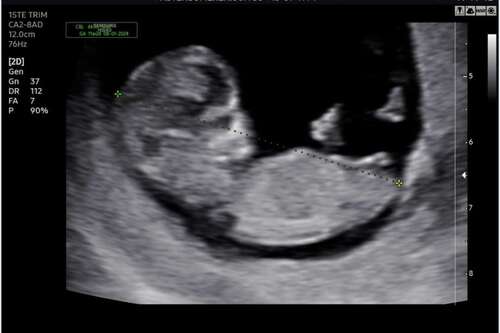

11+3. Is dat rechts dan de nub? Dan zou het een meisje zijn toch? Ik had eigenlijk het idee dat dat een beentje is??

Jaa duidelijk de nub! Voor nu lijkt het op een 馃挆

Is er iemand die de nub kan zien ? Ik zie het namelijk niet haha

Hoe ver ben je hier? Het is erg lastig te zien maar ik zeg voorzichtig 馃挆